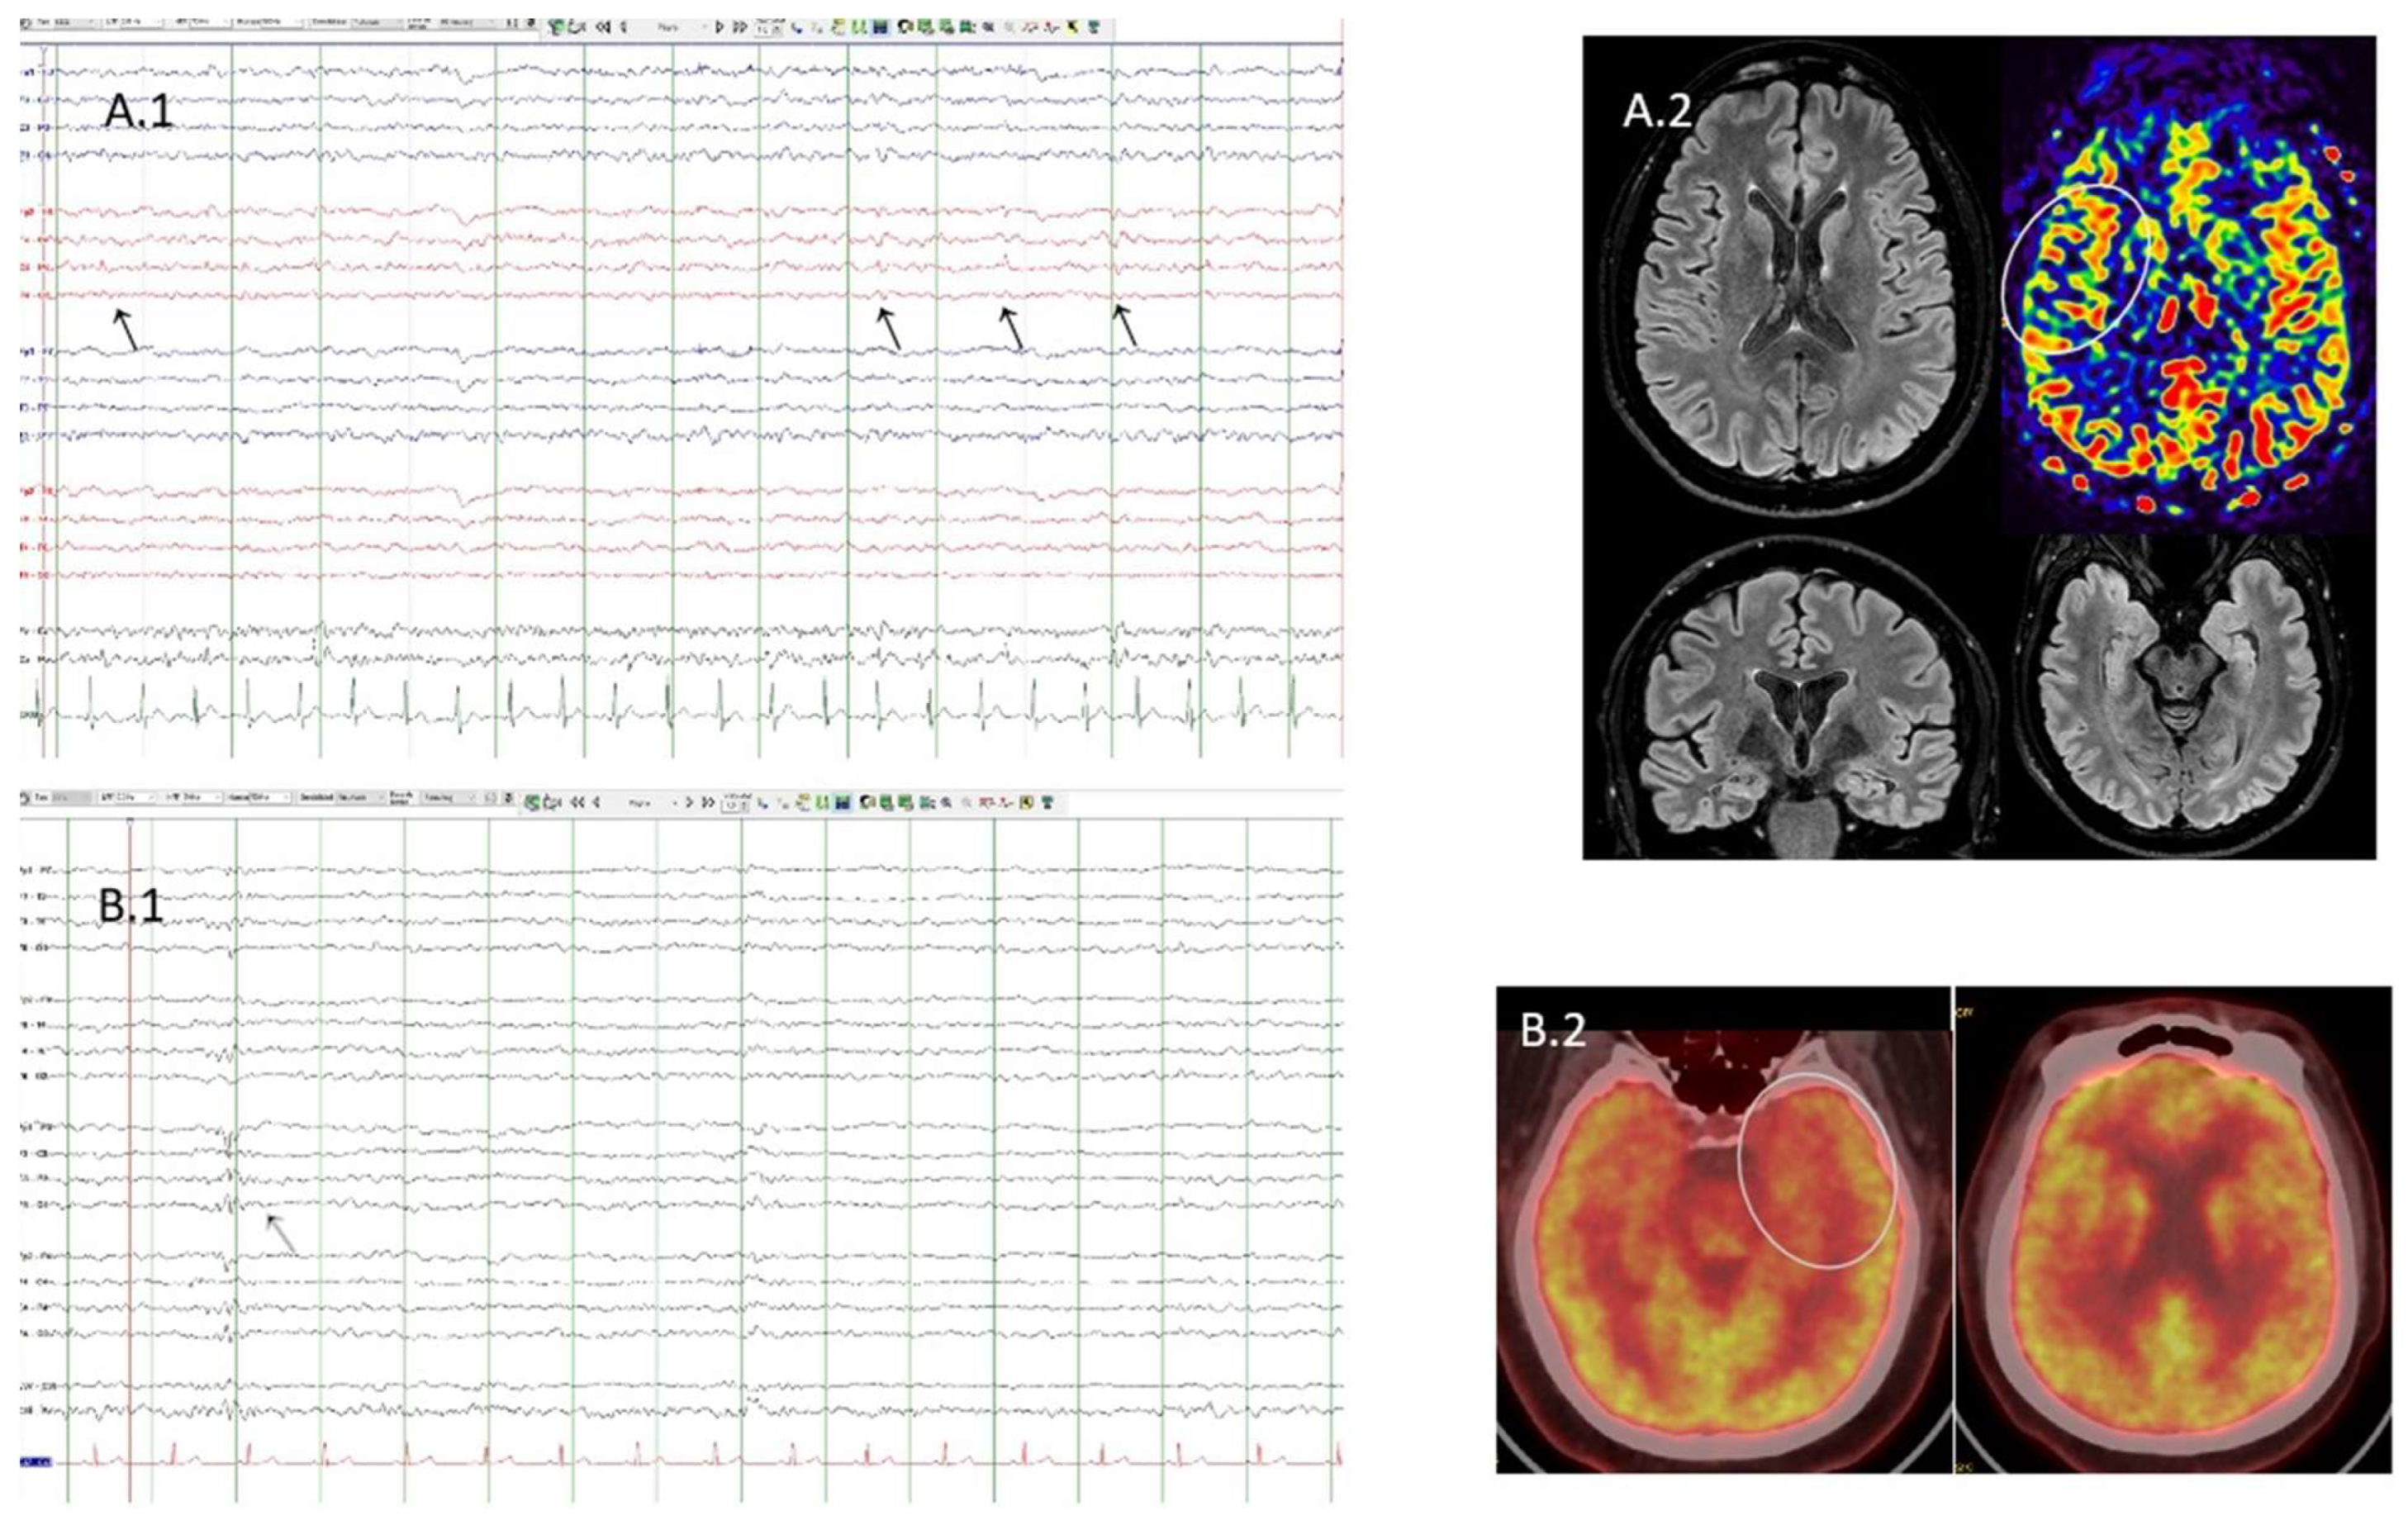

3.2. Case 2

| 2 | F | 25 | 40 | Right Fronto-central (Seizure recorded) | Generalized IIIa | Autoimmune | Nonlesional R. mesiotemporal h. | Hypersalivation-FIAS | CBZ | Mycophenolate mofetil + prednisone + IVIG | No | Pathological | Pathological | AchR, PR3, GAD low titers | PR3+ ANCA vasculitis |

| 3 | M | 11 | 25 | Bilateral fronto-central (Seizures recorded) | Generalized IIa | Post NORSE | Nonlesional | Anarthria+ sensation of auditory plugging FIAS | LCM, CLB BRV, CNB | Prednisone + azatioprine | Yes | Pathological | Pathological | AchR | N.O.R.S.E as debut |